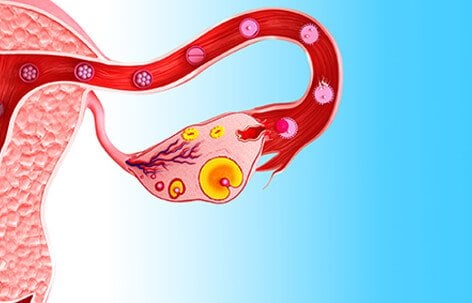

Ovulation is controlled by a series of hormone chain reactions originating from the brain's hypothalamus. Every month, as part of a woman's menstrual cycle, follicles rupture, releasing an egg from the ovary. A follicle is a small fluid sac that contains the female gametes (eggs) inside the ovary. This process of releasing and egg from the ovary an into the Fallopian tube is known as 'ovulation'.

Sometimes a follicle does not release an egg during ovulation, and instead it continues to fill with fluid inside the ovary. This is called a 'follicular cyst'. In other cases, the follicle releases the egg but the sac seals up again and swells with fluid or blood instead of dissolving. This is known as a 'corpus luteum cyst'. Both of these conditions are types of functional ovarian cysts. Functional ovarian cysts are the most common type of ovarian cysts.

There are two types of functional ovarian cysts: follicle cysts and corpus luteum cysts.

Follicular cysts contain a follicle that has failed to rupture and filled with more fluid instead. Corpus luteum cysts occur when the follicle ruptures to release the egg, but then seals up and swells with fluid. Corpus luteum cysts can be painful and cause bleeding. When bleeding occurs in a functional cyst, it is known as a hemorrhagic cyst.